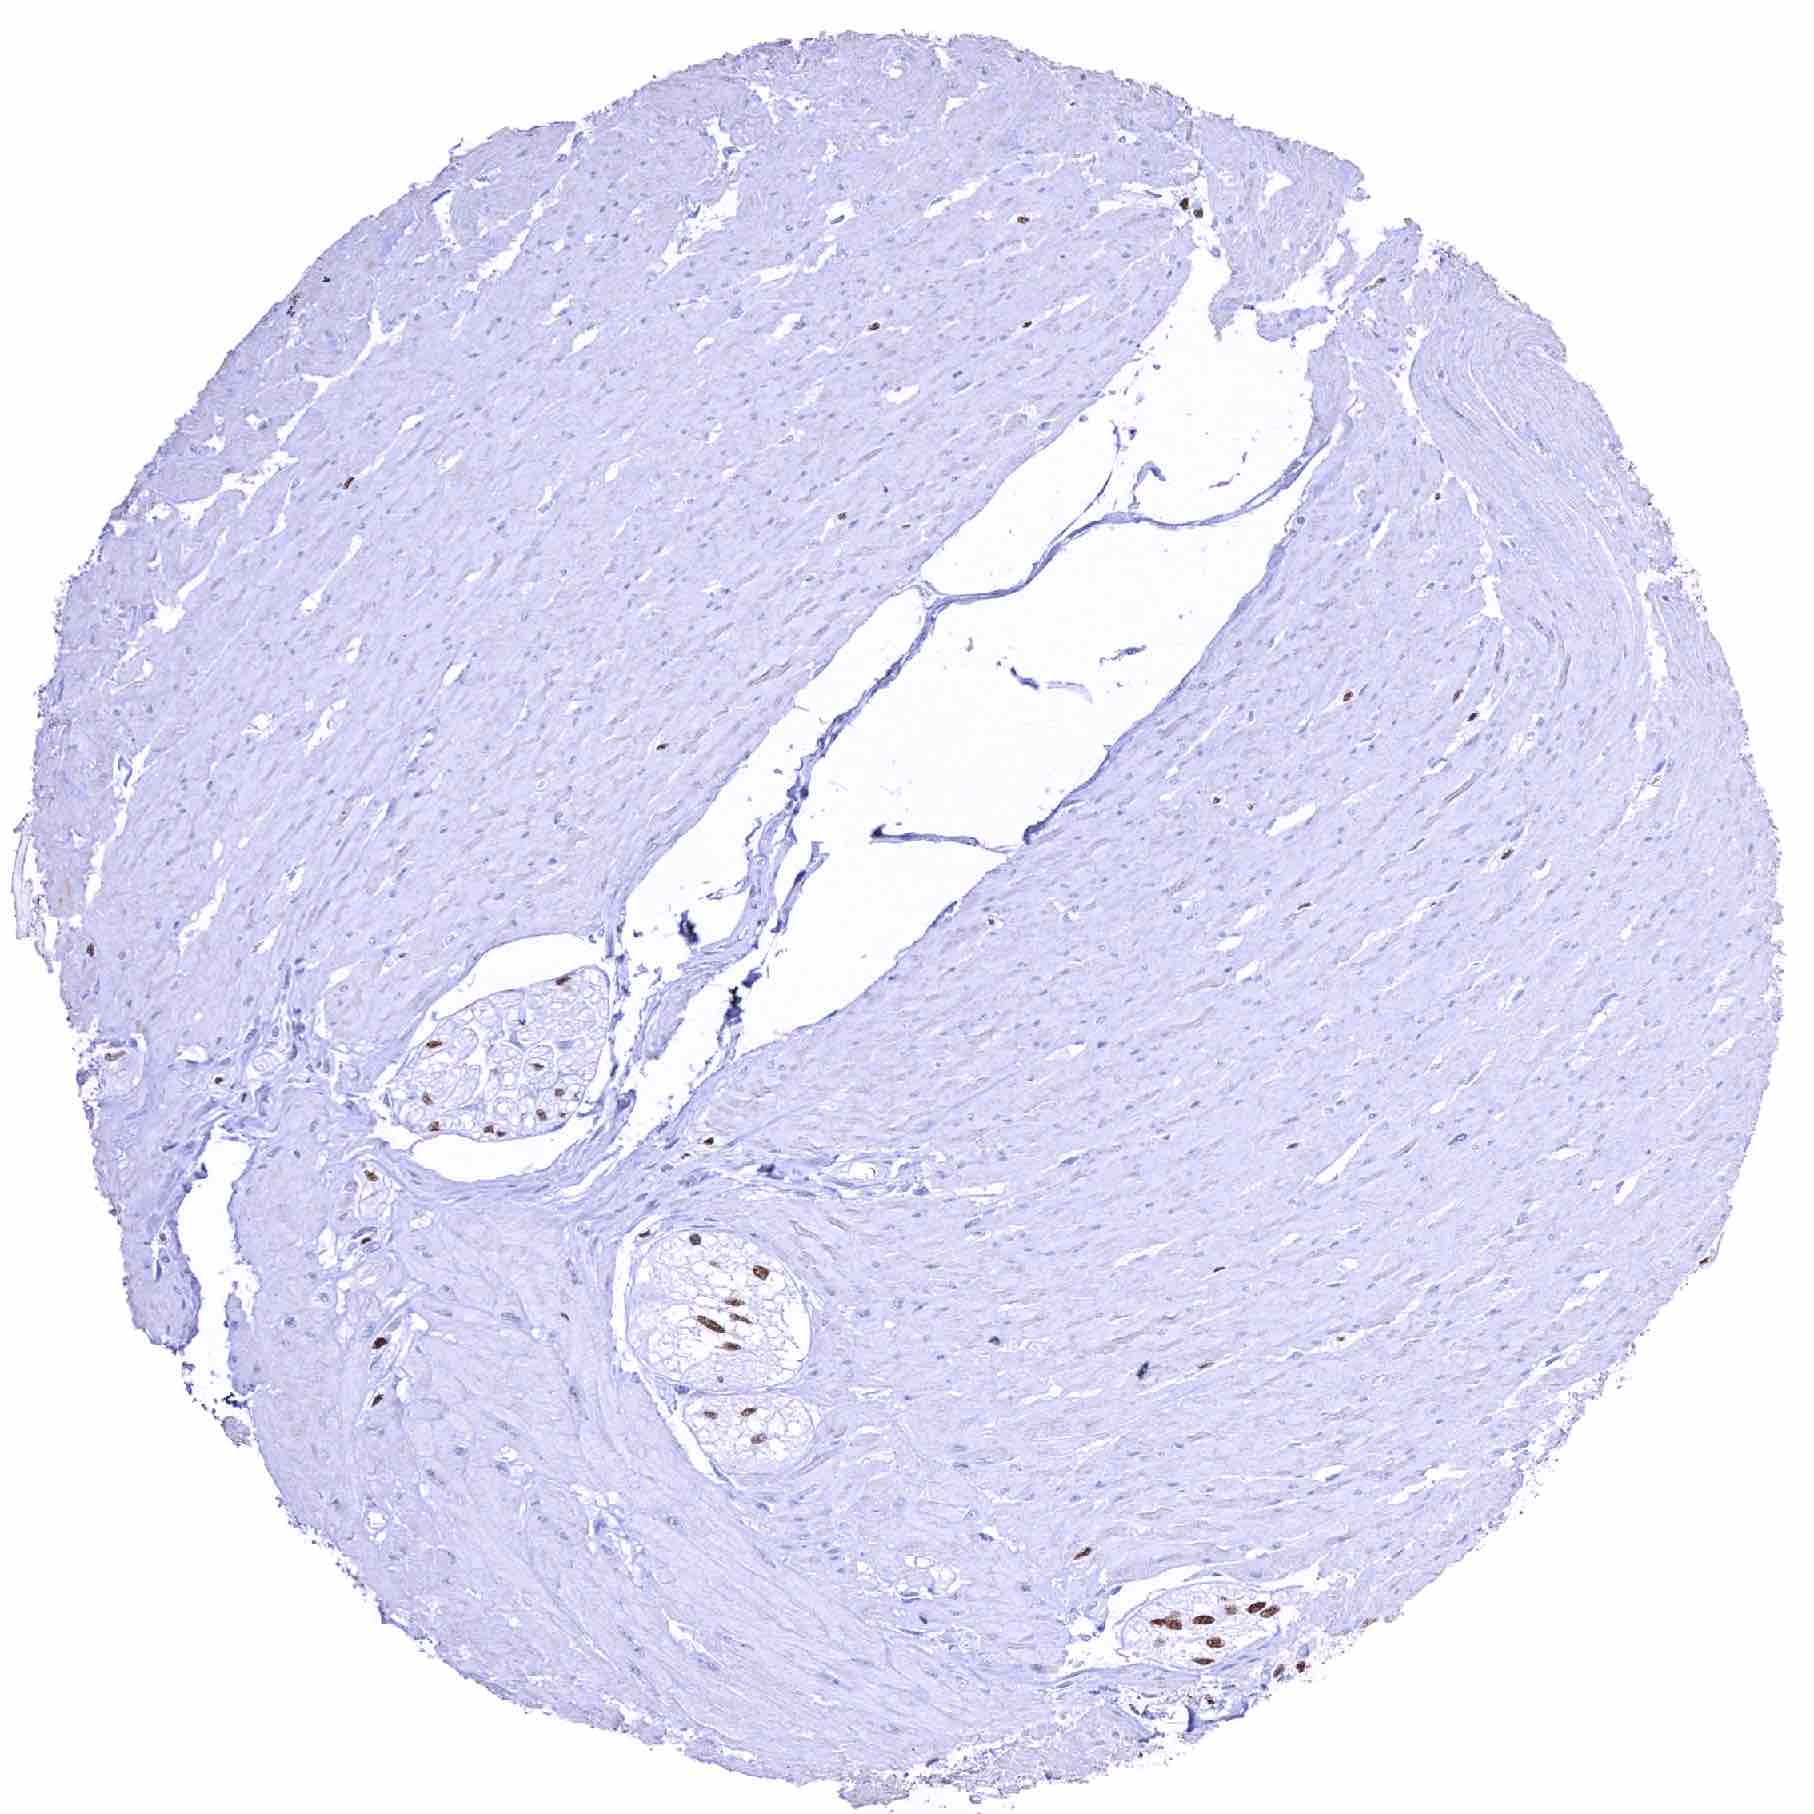

Uterus, myometrium